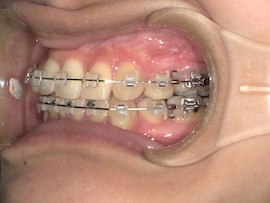

そこから1ヶ月後、

再度レントゲンにて左上親知らずの状態を確認したところ手前の歯に引っかかっていそうだったので、親知らずにもブラケットをつけてバネで押しながら引っ張るように調整してもらいました。